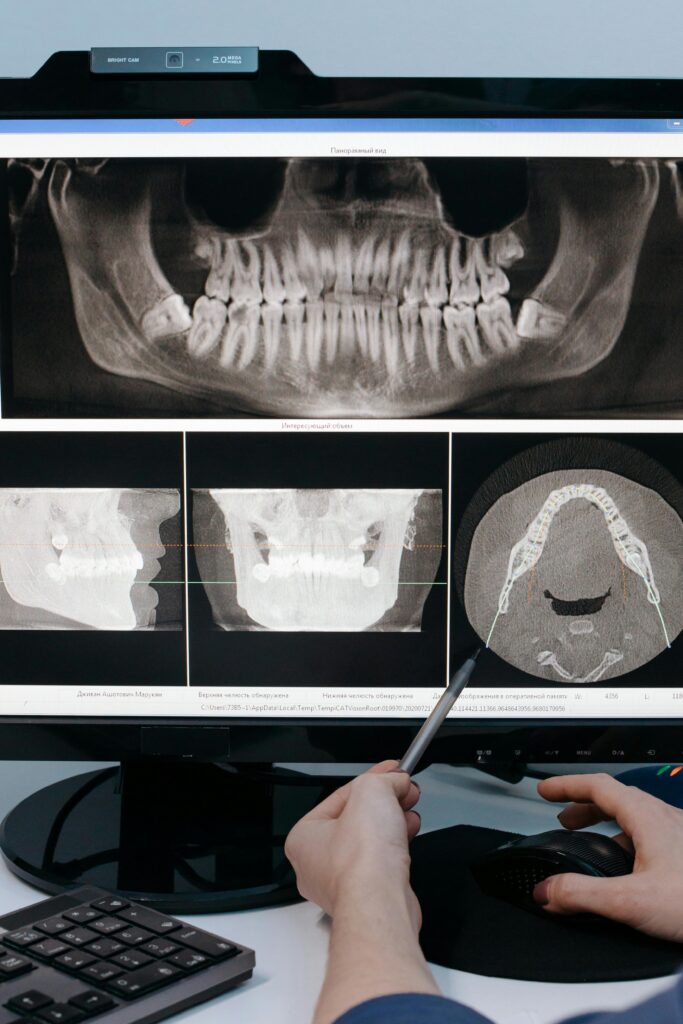

Parodontalstatus

Wir erfassen milimetergenau den Zustand Ihrer Parodontalerkrankung.